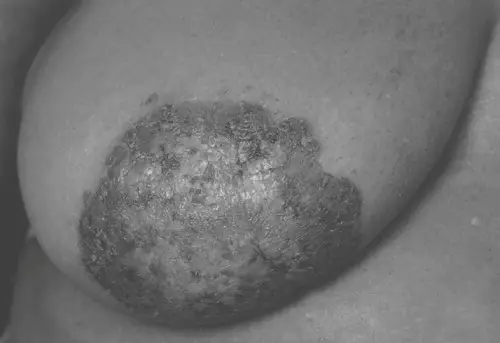

照片顯示之乳房病灶,最有可能為下列何種疾病?

Paget’s disease of the breast:乳頭–乳暈複合區之表皮被原發於乳管的惡性腺癌細胞浸潤,引起慢性濕疹樣、鱗屑結痂性病變,常與潛在的乳管內或浸潤性癌並存。

從影像觀察,病灶局限於乳頭及周圍乳暈皮膚,呈現不規則邊緣的鱗屑、結痂及色素沉著,表面粗糙、局部可見潰瘍或滲液。無明顯整片乳房紅腫或硬結,也不見繃緊的繩索狀硬結或局部觸痛壓痛,乳頭本身尚可辨識但表面被病灶覆蓋。

選項B Paget’s disease

典型表現為乳頭–乳暈部鱗屑樣、結痂或濕疹樣病灶,伴有厚化、潰瘍、滲液或色素異常,常有癢痛或灼熱感。晚期病灶可破壞乳頭形態、出現侵蝕性潰瘍。本題影像所示之不規則鱗屑結痂、色素沉著及範圍,與Page